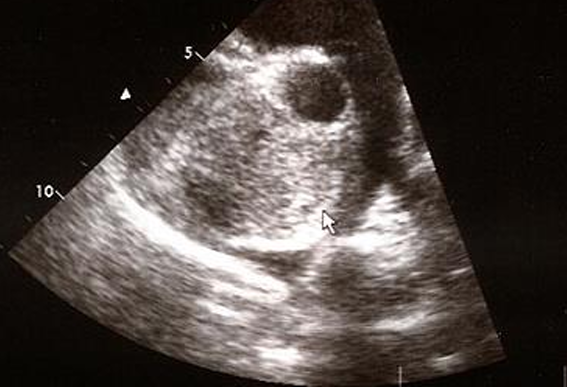

![]() |

| PPDH : ๋ณต๊ฐ ์ ์ฅ๊ธฐ๊ฐ ์ฌ๋ญ ์์ผ๋ก ๋ค์ด๊ฐ โ ์ฌ์ฅ์ด ๋งค์ฐ ์ปค ๋ณด์. ![]() | - ์ ์ฒ์ฑ ์ง๋ณ์ด๋ผ ์ด๋ฆด ๋ ๋ฐ์. (PE๋ ์ด๋ฆด ๋ ์ X) - โ PPDH๋ diaphragm silluette์ด ๋ช ํํ์ง ์์. - โ ์ฅ์ ์ฐจ ์๋ ๊ณต๊ธฐ ์์์ด ๋ณด์ |

DCM![]() | - .. dialation์ด ๋์ด ์์ด์ผ ํจ. |